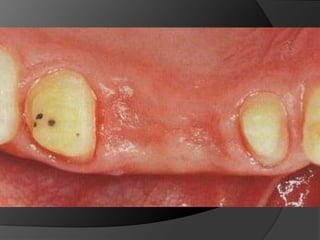

Planificación Del Tratamiento En Restauraciones UnitariasRestauraciones Extracoronarias

Estructura coronaria insuficiente para retener la restauración dentro de la corona del dienteEstructura dentaria defectuosa o socavadaModificar los contornos para mejorar la oclusión o la estética

Planificación Del TratamientoEn Restauraciones UnitariasRestauraciones Extracoronarias

Estructura coronaria insuficientepara retener la restauración dentro de la corona del dienteEstructura dentaria defectuosa o socavadaModificar los contornos para mejorar la oclusión o la estética